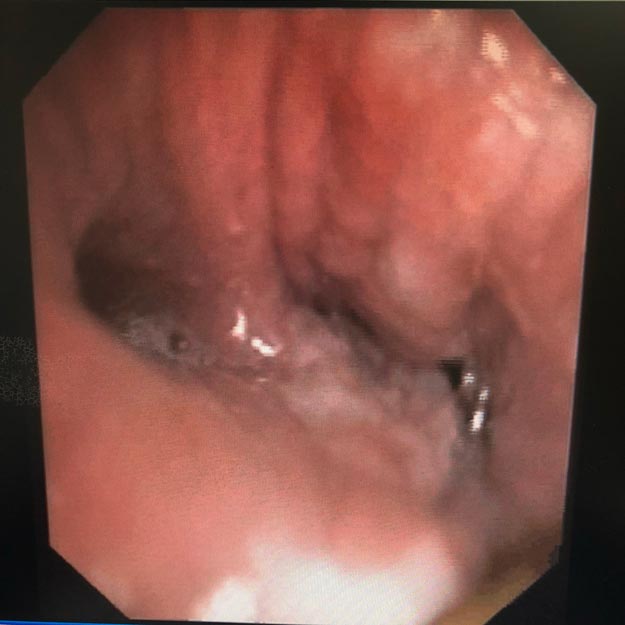

经呼吸内科医师讨论后,决定给予陈阿姨纤支镜下低温等离子消融术,即先将周围肉芽组织烧灼,再将异物取出。经过纤支镜治疗,成功把异物从左下肺支气管取出。但取出异物后发现,由于异物嵌顿时间过长,异物对气管粘膜刺激导致支气管明显狭窄,可能导致反复的阻塞性肺炎和肺功能下降。

(陈阿姨狭窄的支气管)